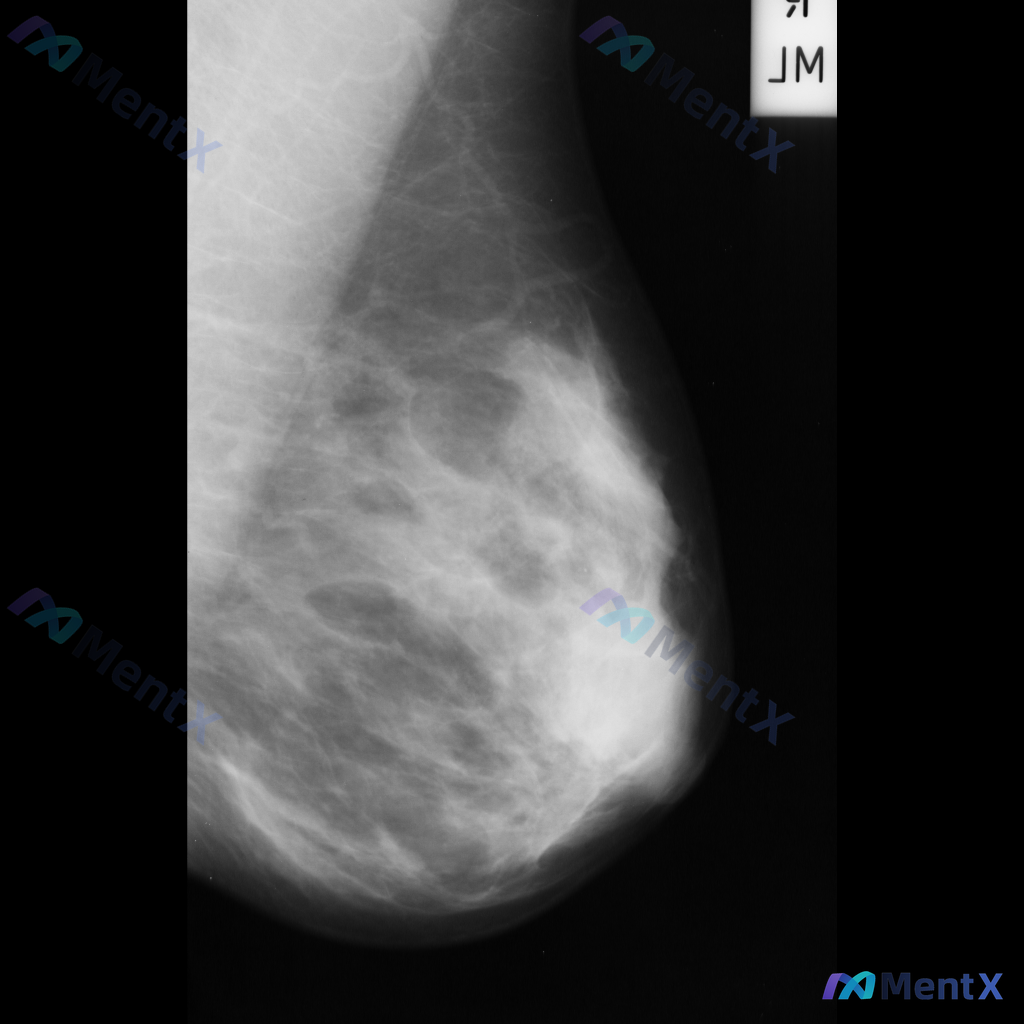

- 影像:右侧乳腺内外斜位(MLO)钼靶

- 背景:致密型乳腺(多量腺体型/不均匀致密)

- 右乳中上象限可见一局限性不对称致密影,形态不规则,边界部分模糊,与周围腺体融合

- 该区域周围可见可疑结构扭曲,小梁结构有牵拉/汇聚表现